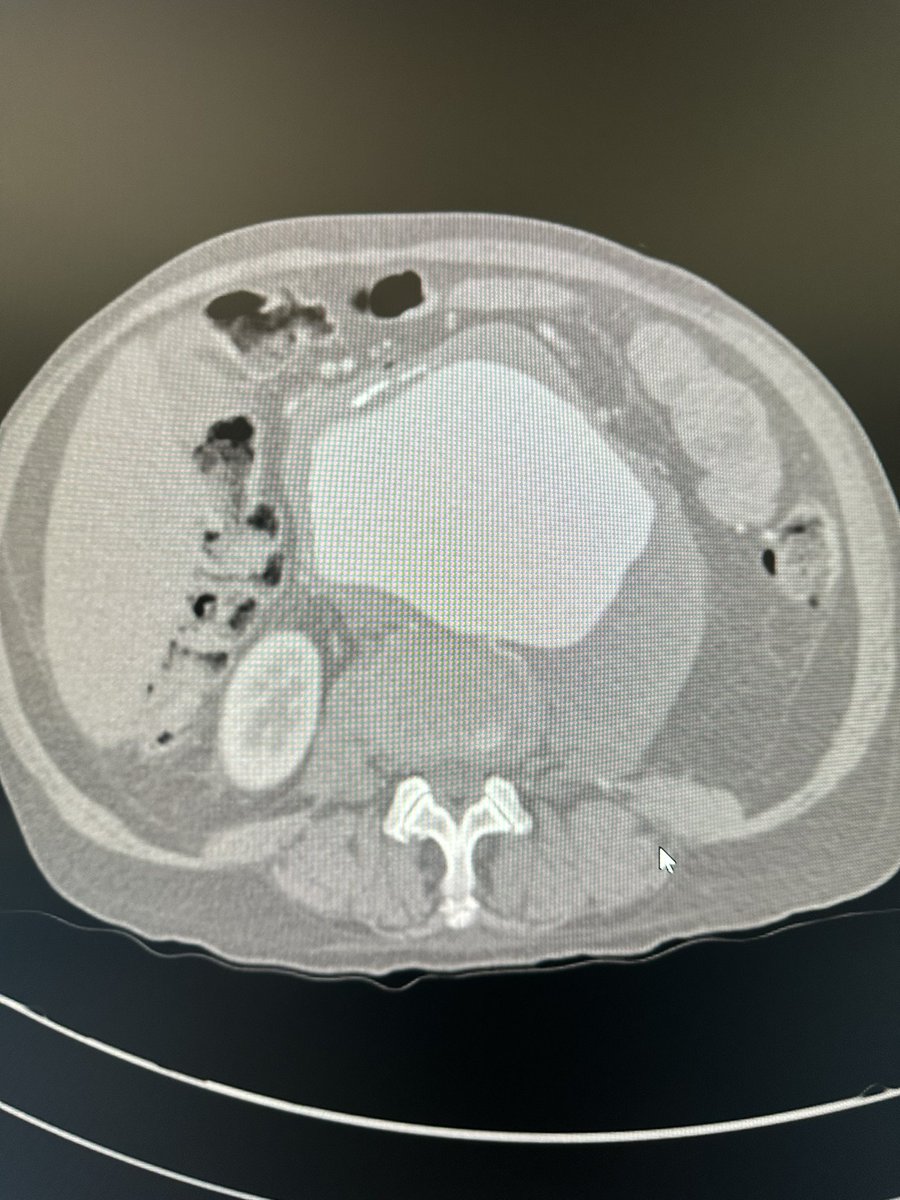

6 pack aorta?! Omentum gone from prior colonic resection after ischemic colitis…referred for an infected ABFB. Bilateral rectus abdominis flaps used to assist in coverage of rifampin soaked graft. @uazphxsurgery